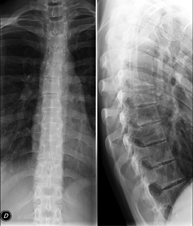

Tècnica que usa els raigs X a través de la qual s'obtenen imatges de la columna dorsal per al seu estudi. Indicacions: traumatisme, mal d'esquena. - RX Columna lumbar

Tècnica que usa els raigs X a través de la qual s'obtenen imatges de la columna lumbar per al seu estudi. Indicacions: ciàtica, traumatisme, dolor lumbar. - RX Sacre-còccix